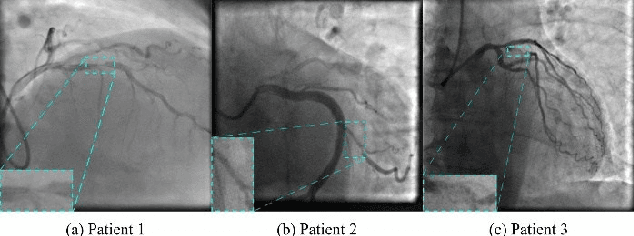

Abstract:In the era of digital medicine, medical imaging serves as a widespread technique for early disease detection, with a substantial volume of images being generated and stored daily in electronic patient records. X-ray angiography imaging is a standard and one of the most common methods for rapidly diagnosing coronary artery diseases. The notable achievements of recent deep learning algorithms align with the increased use of electronic health records and diagnostic imaging. Deep neural networks, leveraging abundant data, advanced algorithms, and powerful computational capabilities, prove highly effective in the analysis and interpretation of images. In this context, Object detection methods have become a promising approach, particularly through convolutional neural networks (CNN), streamlining medical image analysis by eliminating manual feature extraction. This allows for direct feature extraction from images, ensuring high accuracy in results. Therefore, in our paper, we utilized the object detection method on X-ray angiography images to precisely identify the location of coronary artery stenosis. As a result, this model enables automatic and real-time detection of stenosis locations, assisting in the crucial and sensitive decision-making process for healthcare professionals.